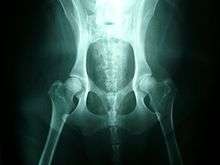

Hip dysplasia in a Labrador Retriever

Normal hips, for comparison